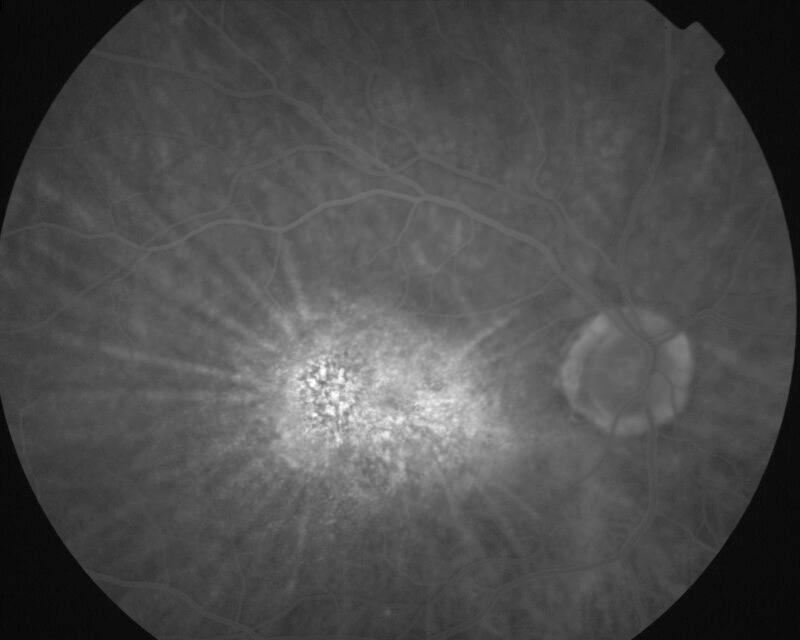

IM000018.jpg